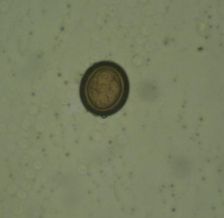

วัดความรู้ว่ารู้จักไข่พยาธิแค่ไหน